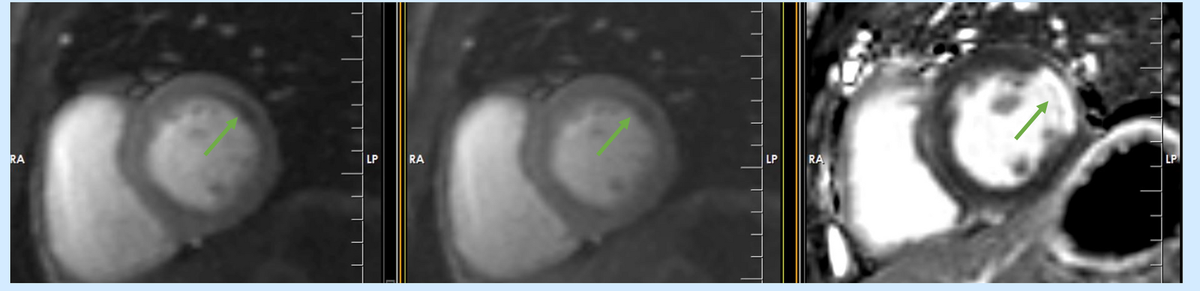

How to do? Stress perfusion CMR